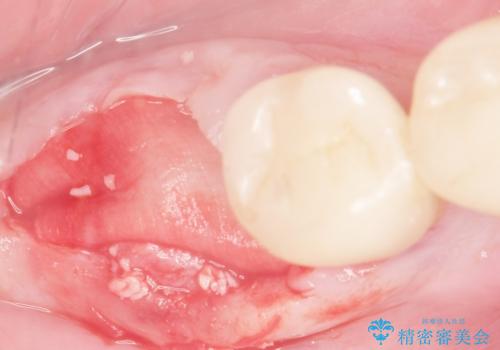

- 奥歯の違和感を主訴に来院された患者様です。

精査したところ、右下の奥歯は大きなう蝕により保存不可能な状態でした。

患者様のご希望により、抜歯後インプラント治療を行いました。